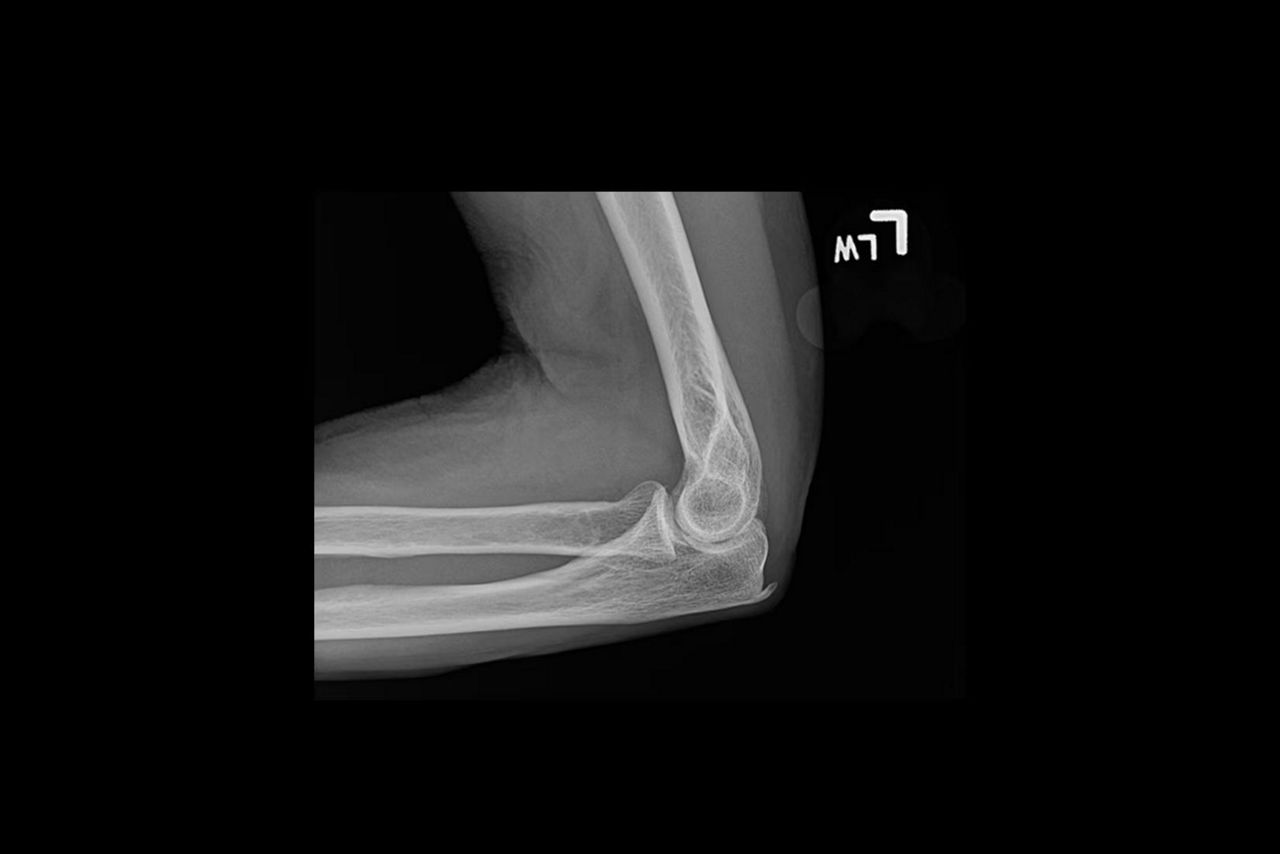

Exceptional detail

Acheive outstanding clarity and anatomical detail across image types

Helix™ Advanced Image Processing offers unparalleled sharpness, balanced contrast, and optimal brightness, even in the face of dose and patient anatomy variations, as well as challenging metal implants. Available on all of our fixed and mobile X-ray systems, Helix provides consistent performance regardless of exposure technique or exam conditions.